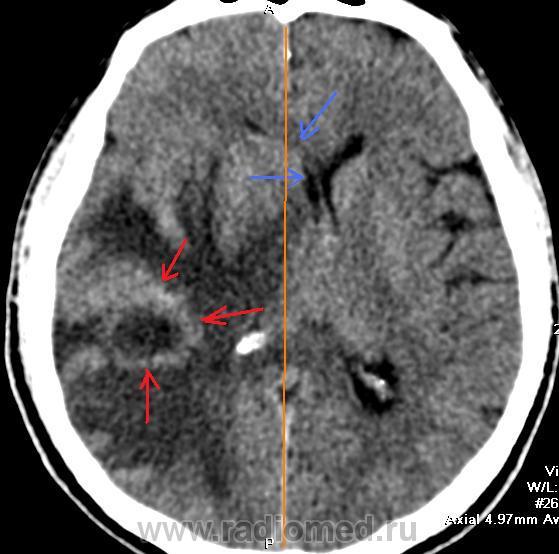

Пол пациента: Мужской пол Тип патологии: Злокачественное новообразование Область исследования: Череп и головной мозг Методы исследования: КТ Предсталяю типичный случай метастаза рака легкого в головной мозг. Кольцевидное образование (красные стрелки) с большим перифокальным отеком, сдавление и смещение желудочков мозга (зеленые стрелки). Пт, 23/10/2009 - 22:56 #1 Наталия Не на сайте Был на сайте: 8 лет 7 месяцев назад Зарегистрирован: 30.07.2008 - 13:24 Публикации: 538 Как хорошо видно и очень информации много. Спасибо автору случая.